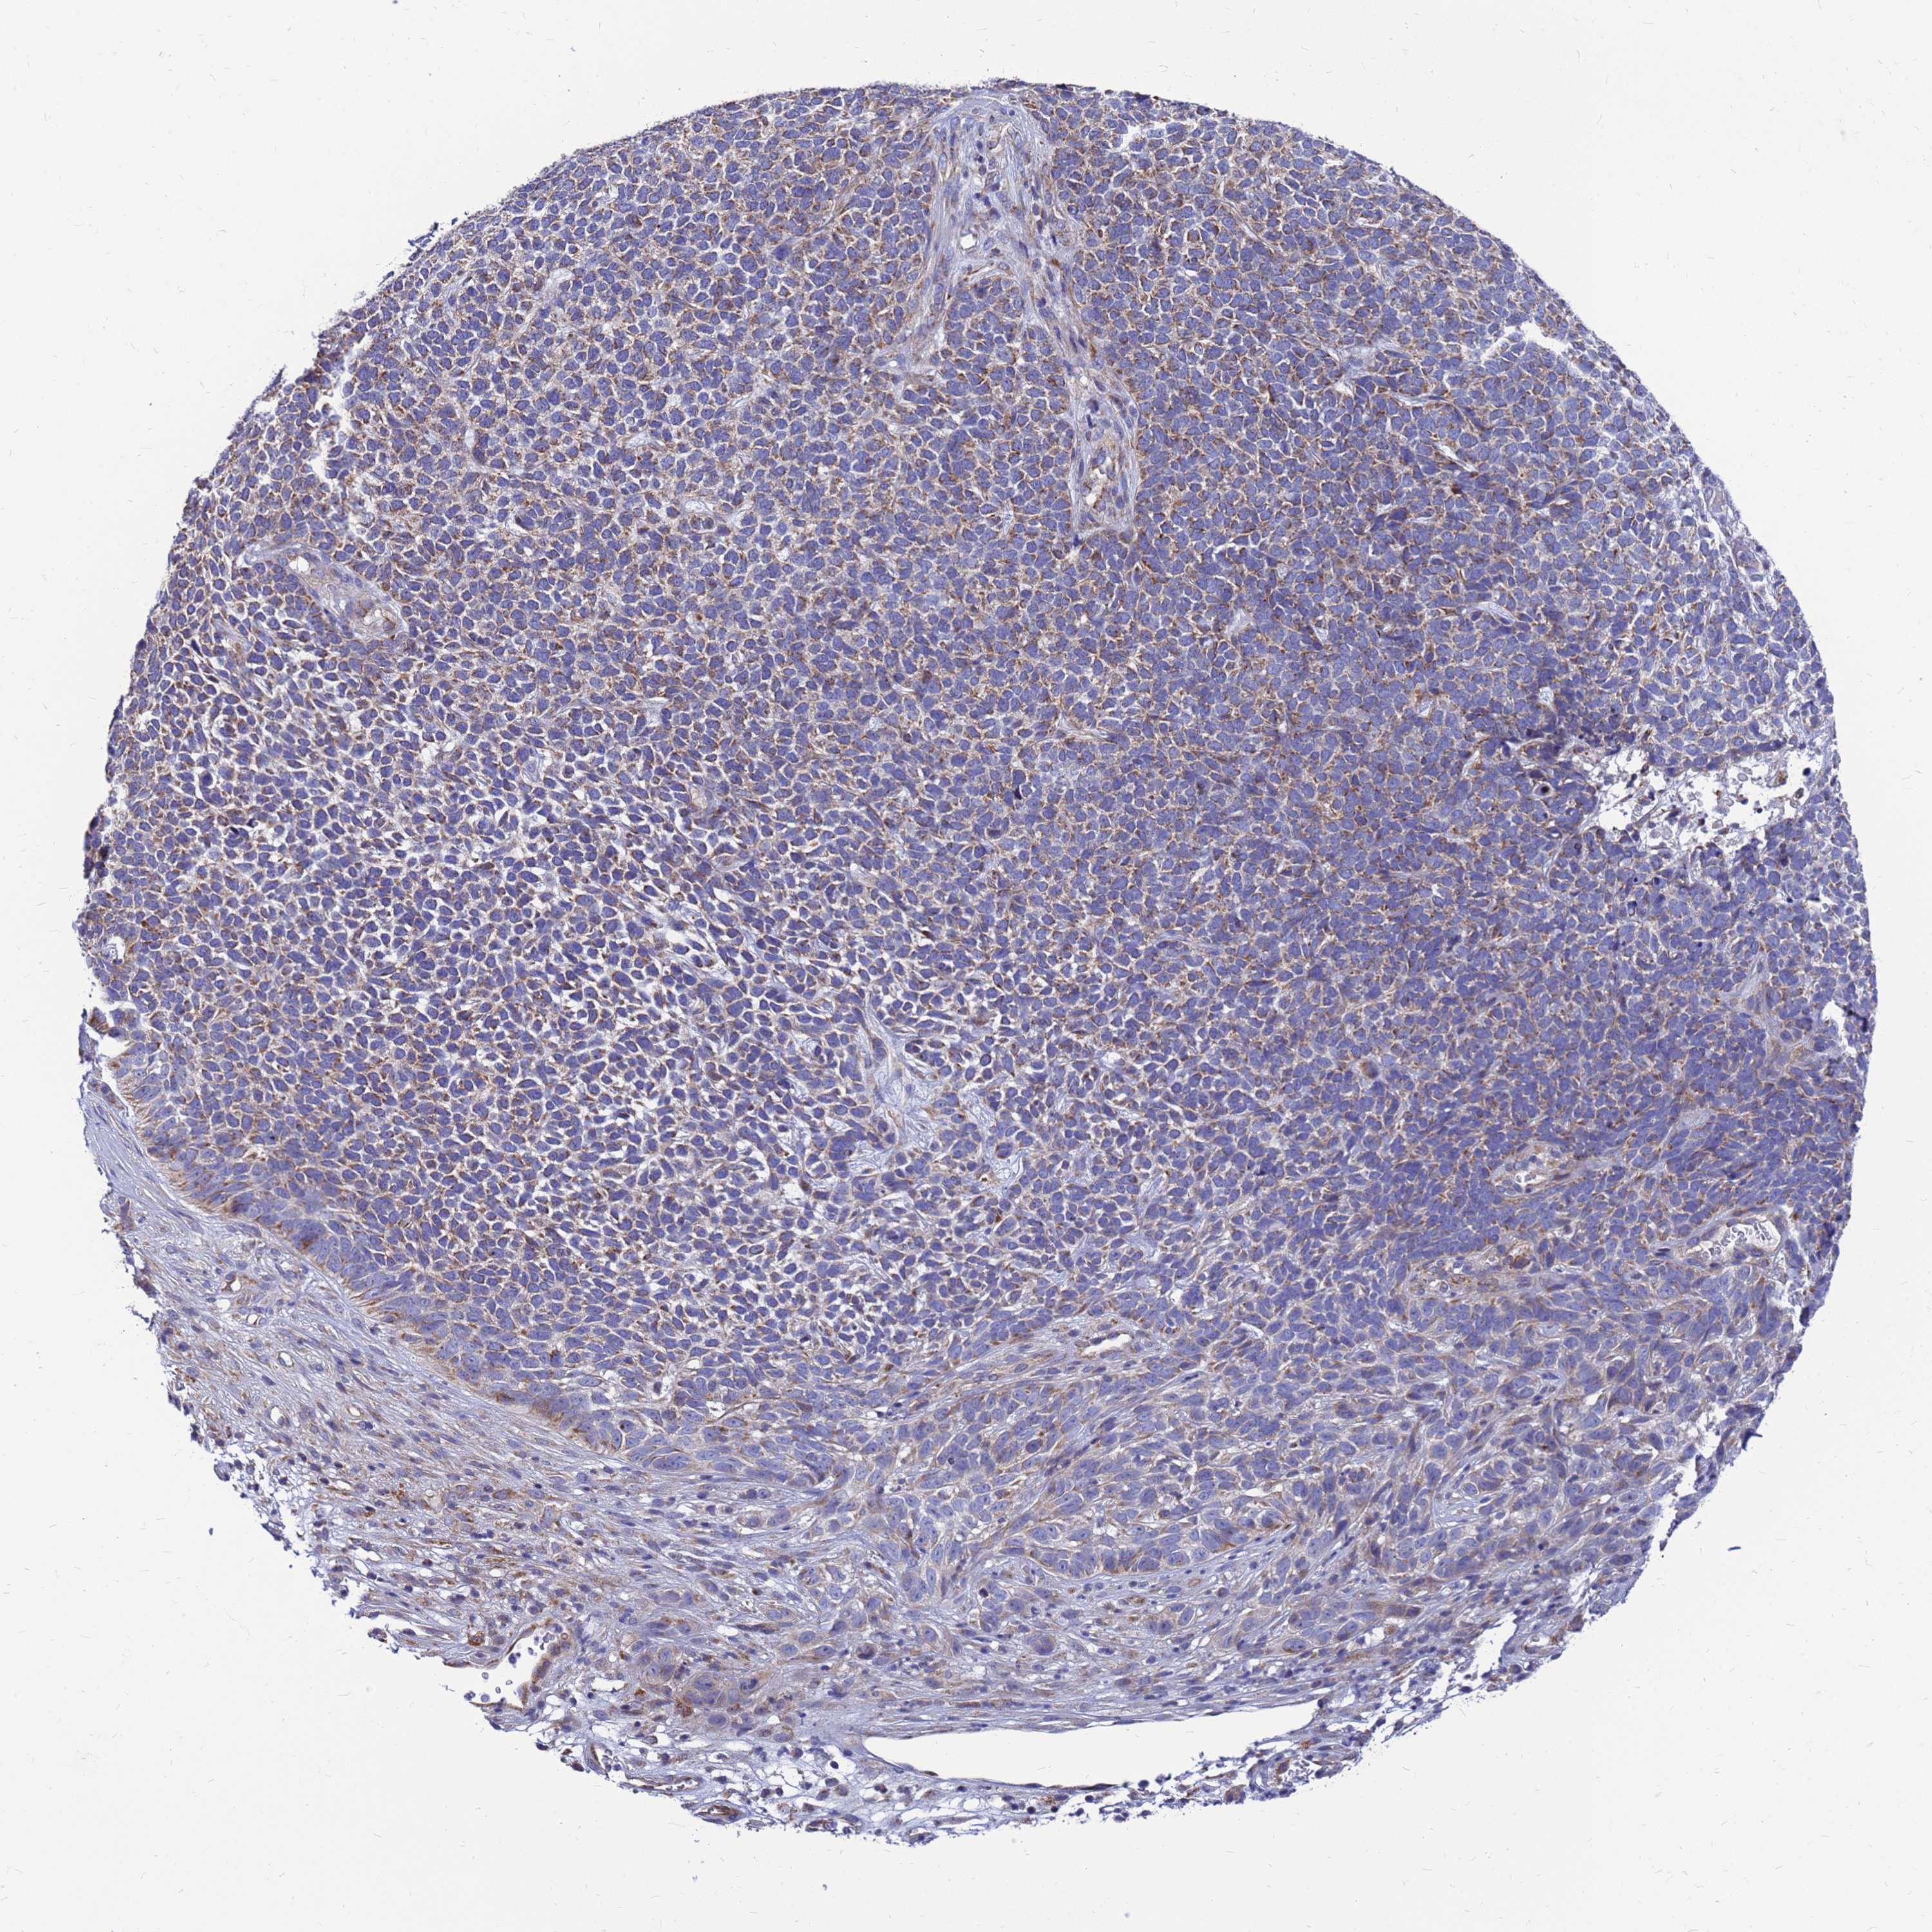

Basal cell and squamous cell cancer

SKIN CANCER - Protein expressioni

A mouse-over function shows sample information and annotation data. Click on an image to view it in a full screen mode. Samples can be filtered based on level of antibody staining by selecting one or several of the following categories: high, medium, low and not detected. The assay and annotation is described here.

Antibody stainingi

Antibody staining in the annotated cell types in the current human tissue is reported as not detected, low, medium, or high, based on conventional immunohistochemistry profiling in selected tissues. This score is based on the combination of the staining intensity and fraction of stained cells.

Each image is clickable and will lead to virtual microscopy that enables deeper exploration of all samples and also displays staining intensity scores, fraction scores and subcellular localization as well as patient and tissue information for each sample.

Antibody HPA045866

Staining

High

Medium

Low

Not detected

Intensity

Strong

Moderate

Weak

Negative

Quantity

>75%

75%-25%

<25%

None

Location

Nuclear

Cytoplasmic/membranous

Cytoplasmic/membranous,nuclear

Squamous cell carcinoma, NOS